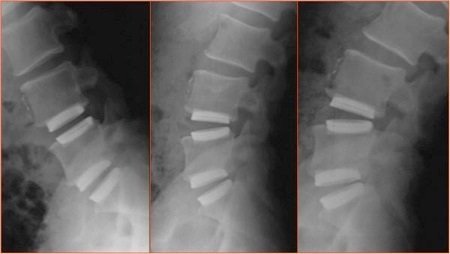

Caselli described another Tsunami innovation – so-called "lobster spacers" (image 3 and 4) – self-spreading spacers that can be used between intervertebral discs in surgical spinal column reconstruction (image 5). The spreading mechanism developed by Tsunami is something of a miracle of manufacturing: it consists of a gearbox with a central screw and side gears that spreads apart two wings (images 6a and b). Creating lobster spacers with perfectly aligned surfaces is possible thanks to the LaserCUSING process, using an Mlab Cusing R system from Concept Laser. Its highly smooth – nearly polished – surface ensures significantly less excrescence in the tissue. A remarkable aspect of the manufacturing technology, according to Caselli, is the ability to produce multiple copies of this complex, movable part at the same time. "LaserCUSING gives us time advantages, advantages in cost structure and is also much easier, under cleanroom conditions, than conventional manufacturing strategies. In addition, machine solutions from Concept Laser provide excellent performance and a high level of safety when working with reactive materials such as titanium or titanium alloys."